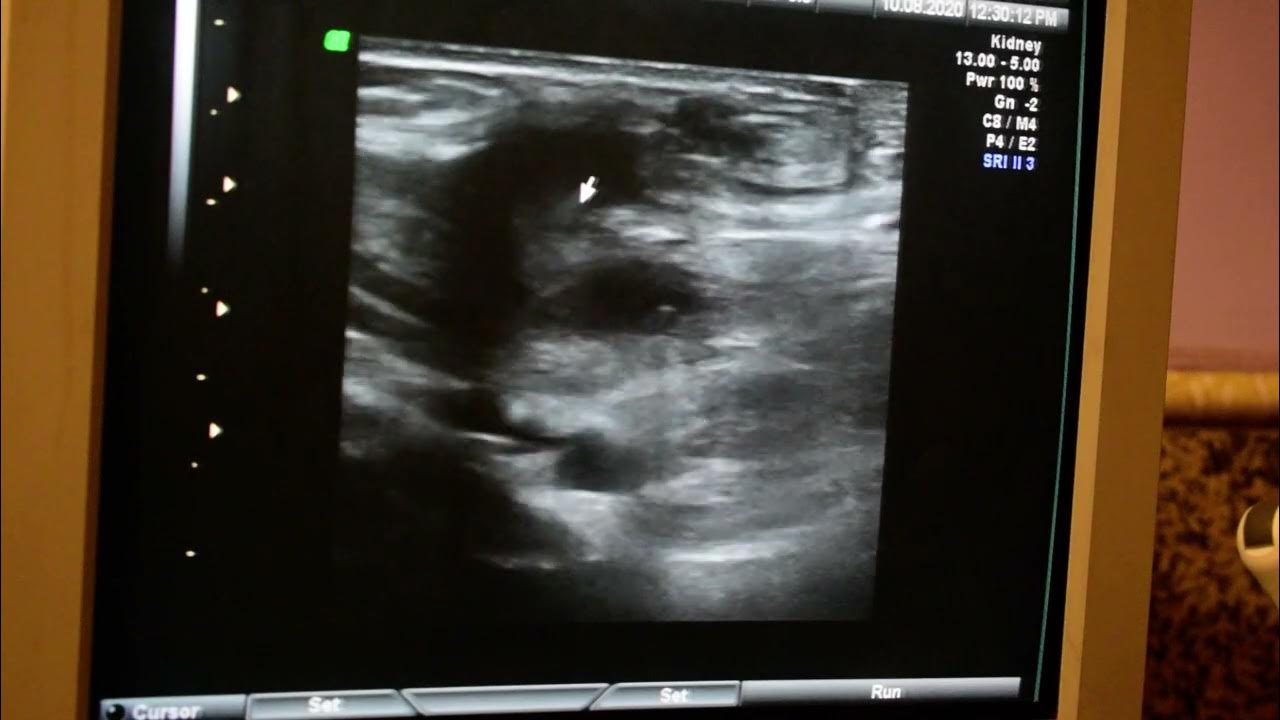

suture granuloma ultrasound by Dr.Haissam Aref, DMS, MSc Ultrasound

suture granuloma ultrasound by Dr.Haissam Aref, DMS, MSc Ultrasound Suture Granulation Tissue as a rule, the simplest method of wound treatment for acute and clean wounds without tissue loss is primary. treatment may include debridement and wound dressings that promote granulation, tissue preservation,. the advancing epidermal wound tongue must also cut a pathway between the scab and the wound. This leads to raised red patches of tissue. migrating. Suture Granulation Tissue.